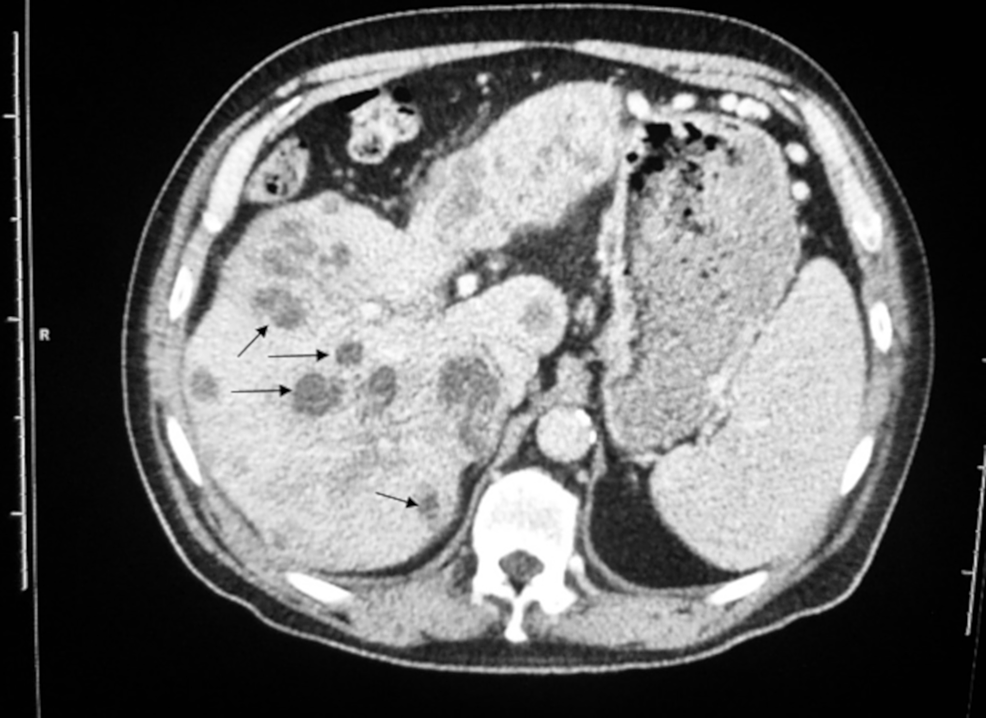

From www.cureus.com

Cureus Streptococcus mitis Abscesses Mimicking Liver Metastases Strep Infection Liver there are more than 120 strains of group a streptococcus bacteria, which is the bacteria that causes group a streptococcal. group b streptococcus (group b strep or gbs) is a bacterium that occurs naturally in the gastrointestinal and genital tracts (vagina, uterus, and. pyogenic liver abscesses usually develops in the context of biliary disease, portal pyemia of. Strep Infection Liver.

Streptococcus mitis Abscesses Mimicking Liver Metastases Cureus Strep Infection Liver the clinical predictors of death during or following infection are advanced. pyogenic liver abscesses usually develops in the context of biliary disease, portal pyemia of various causes,. there are more than 120 strains of group a streptococcus bacteria, which is the bacteria that causes group a streptococcal. streptococcus intermedius is usually found as a solitary isolate.. Strep Infection Liver.